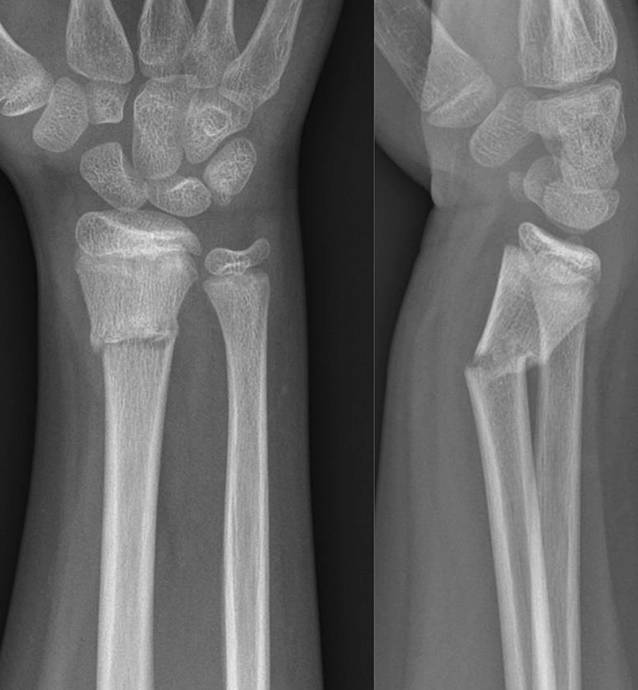

Abb. 10

11-jähriger Junge, Sturz mit Skateboard. Distale metaphysäre vollständige Radiusfraktur mit Achsenknick nach dorsal von rund 30°. Am Unfalltag unter Analgetikagabe zur primären Schmerzbehandlung Anlage eines Oberarmspaltgipsverbandes in Vertikalextension mit gefühlvollem Anmodellieren entgegen der Fehlstellung